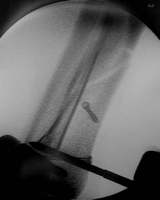

Röntgenkontrolle mit dem Bildwandler im OP

Achsengerechte Stellung der Fraktur